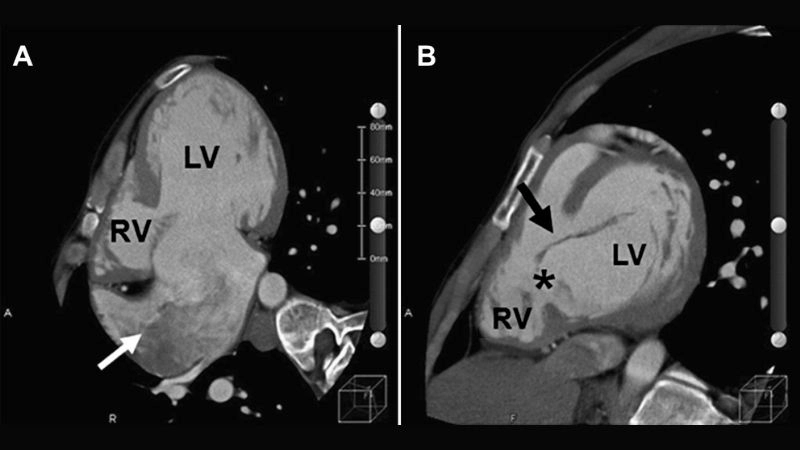

Images Visual Examples Of Atrioventricular Canal Defect (Endocardial Cushion Defect)

Atrioventricular Canal Defect is a congenital heart disease where the walls separating chambers do not form properly, leading to mixing of blood and heart inefficiency.